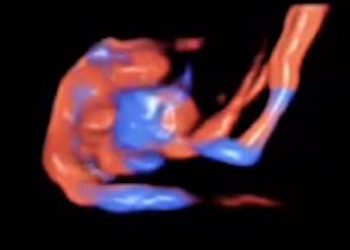

How To Do Giugno 2020: le arterie uterine

Finalmente on line il nuovo video "How to do" del mese di Giugno, sul campionamento delle arterie uterine! Grazie a...